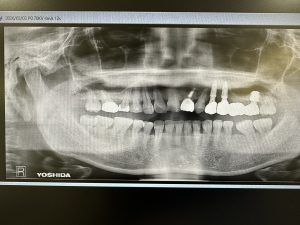

以下の画像は、本日定期検査の方

オペから9ヶ月位の画像、良いね👍👍

デンサーバーでのリフト、採血濃縮血漿板使用

異物の人工骨は一切使わない

目利きある先生方には分かるはず!